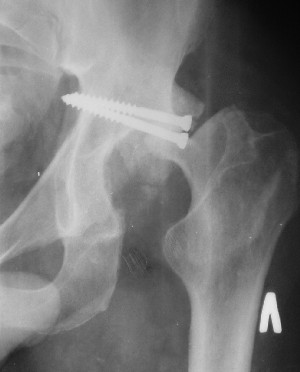

Привет! Вот недавно прооперировали похожий на ваш случай - впадина + шейка (правда у нас впадина поперечный+задний край). После травмы прошло 4 недели. мужчине 46 лет. С такой комбинацией все показания к первичному протезированию. Морально и технически мы к этому уже созрели.Но больной не собрал денег на протез. Выполнили остеосинтез впадины и шейки, прекрасно понимая, что головка вскоре рассосется, мы хотя бы надемся что к этому времени таз срастется, как говорится создали все условия для дальнейшего протезирования (может, и протез в последующем подешевле будет, в смысле, без укрепляющего кольца?). Привет Рункову!

Привет Алекей! Сделано неплохо, поздравляю, хотя второй винтик можно было бы и подлиннее в шейку загнать! Пара вопроов: доступ такой же? головка была свободной или висела на капсуле?

Согласен, можно было и подлиннее. Доступ такой же - чрезвертельный, только разрез кожи прямой (а не Y, чего то я разницы не ощущаю). Головка была абсолютно свободной (то есть во время остеосинтеза таза лежала в стакане и не мешалась). Шансов, что она прирастет 0,00001%. Хотели даже выбросить, но привинтили как временный биологический протез (читай свободный трансплантат), чтоб на период срастания таза бедро проксимально не ушло (может ортопеды потом спасибо скажут). Ну а у вас первичное протезирование при переломе впадины тоже пока полько в планах?